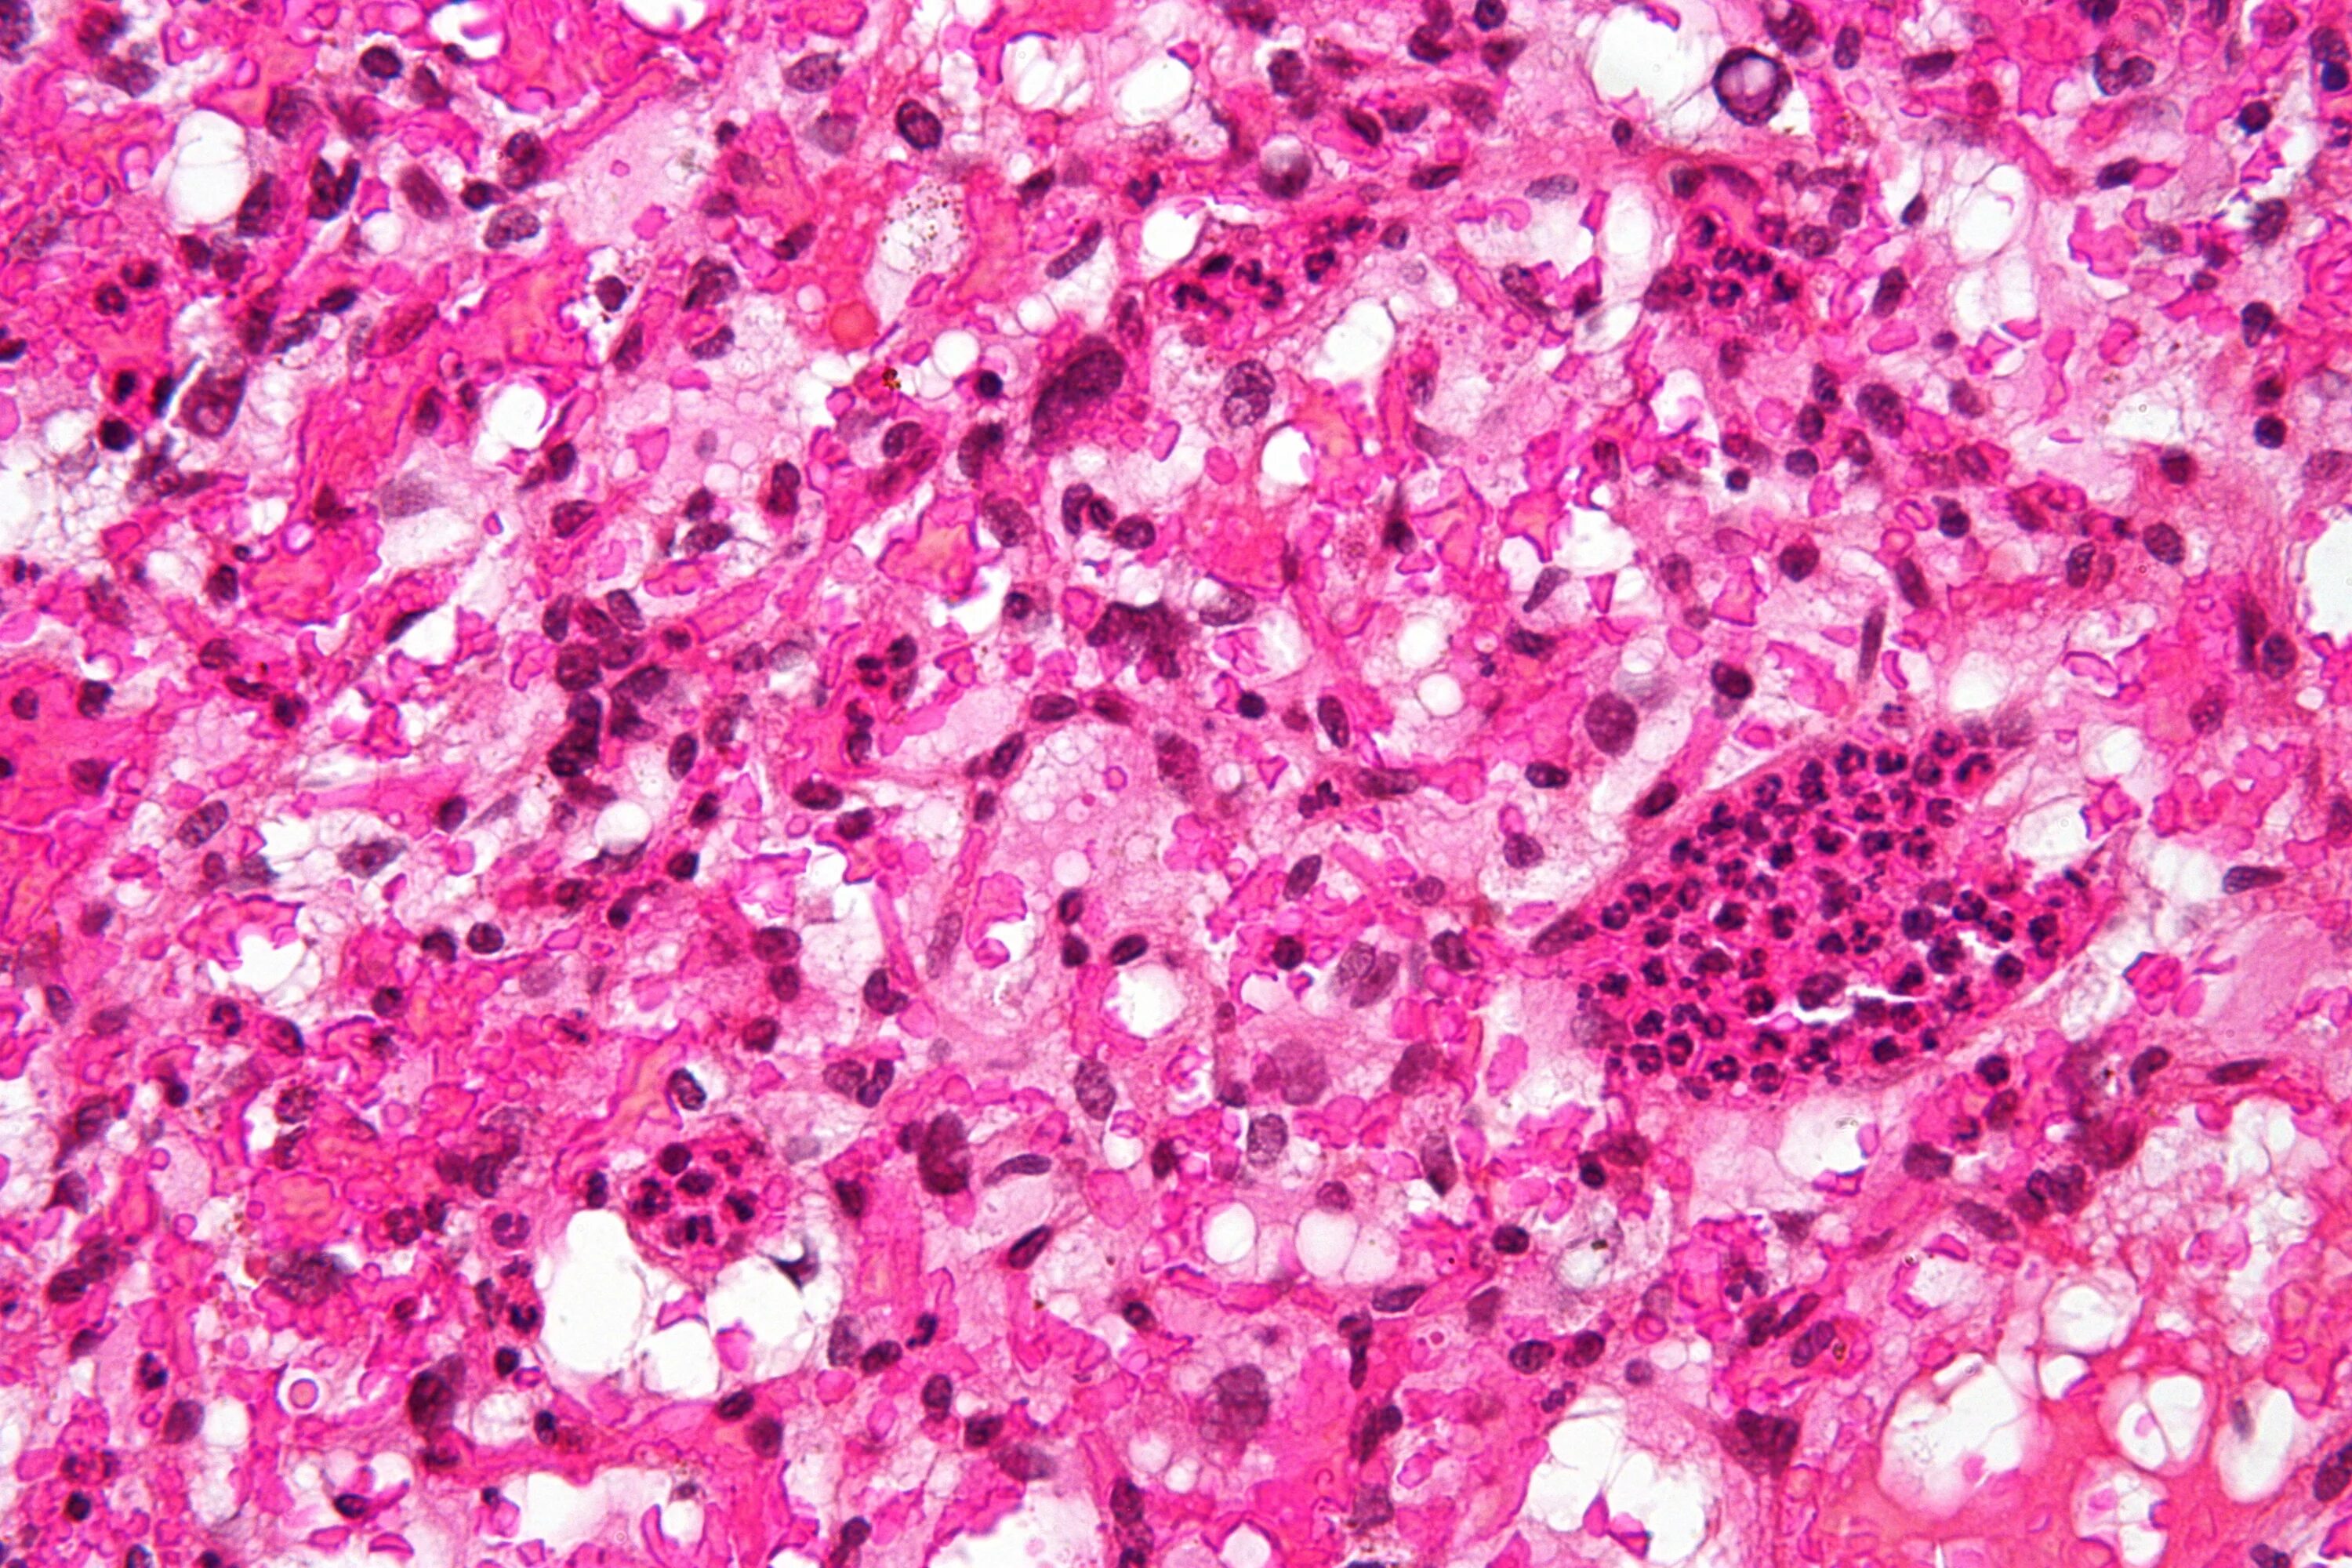

Патанат